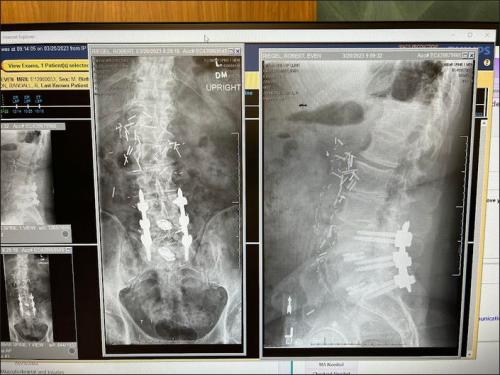

That's a helluva break there young man !!!! Let it mend and be Patient.